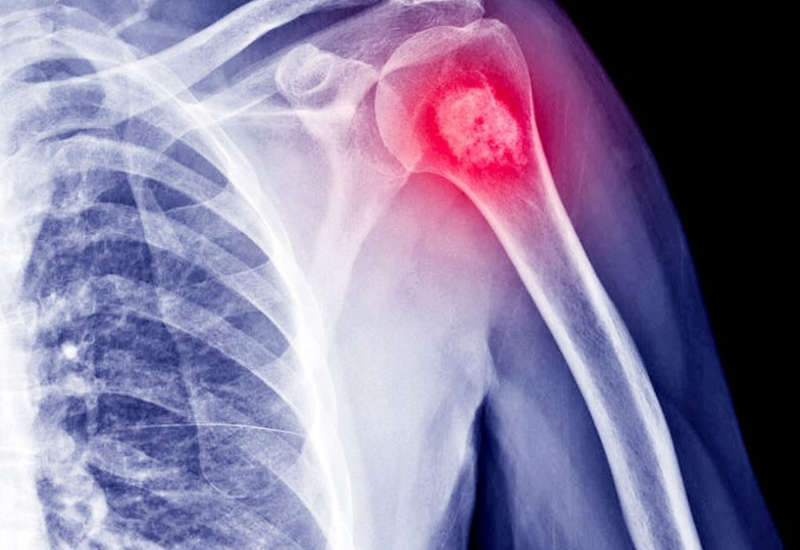

Tế bào ung thư phát triển nhanh bất thường, hình thành nên khối u trong tinh hoàn